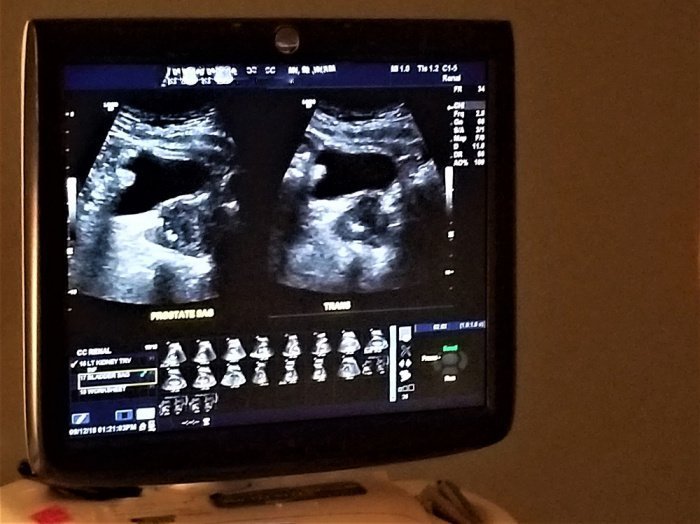

Мы оснащены органами, которые не видимы нашему глазу, но сбой которых может привести к серьезным последствиям для нашего здоровья. Возьмем к примеру – почки. Почки выполняют важную роль в нашем организме и крайне необходимы для жизнедеятельности человека. У большинства людей две почки.